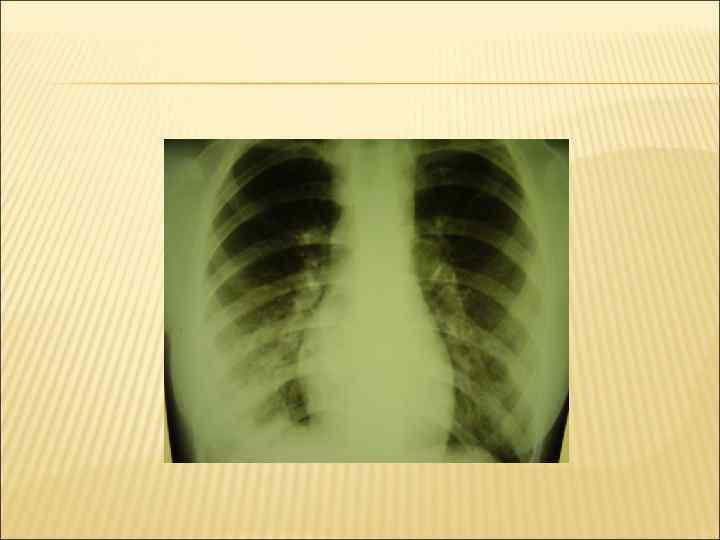

Мозаичность» перкуторного звука Жесткое, может быть ослабленное. Локальные влажные, мелко- и среднепузырчатые хрипы На фоне измененного легочного рисунка различного размера и локализации очаговые тени. (рентгенологически).

СИНДРОМ КРУПНООЧАГОВОЙ ИНФИЛЬТРАЦИИ Кашель, учащенное, затрудненное дыхание (одышка). Повышение температуры тела, Ухудшение самочувствия, слабость, изменение поведения Те же симптомы что и при мелкоочаговой, но они более выражены. Большие зоны притупления легочного звука.

Голосовое дрожание над очагом – усилено Бронхиальное дыхание. Крепитация. Бронхофония - усилена. На фоне измененного легочного рисунка массивные области затемнения (иногда целая доля легкого)